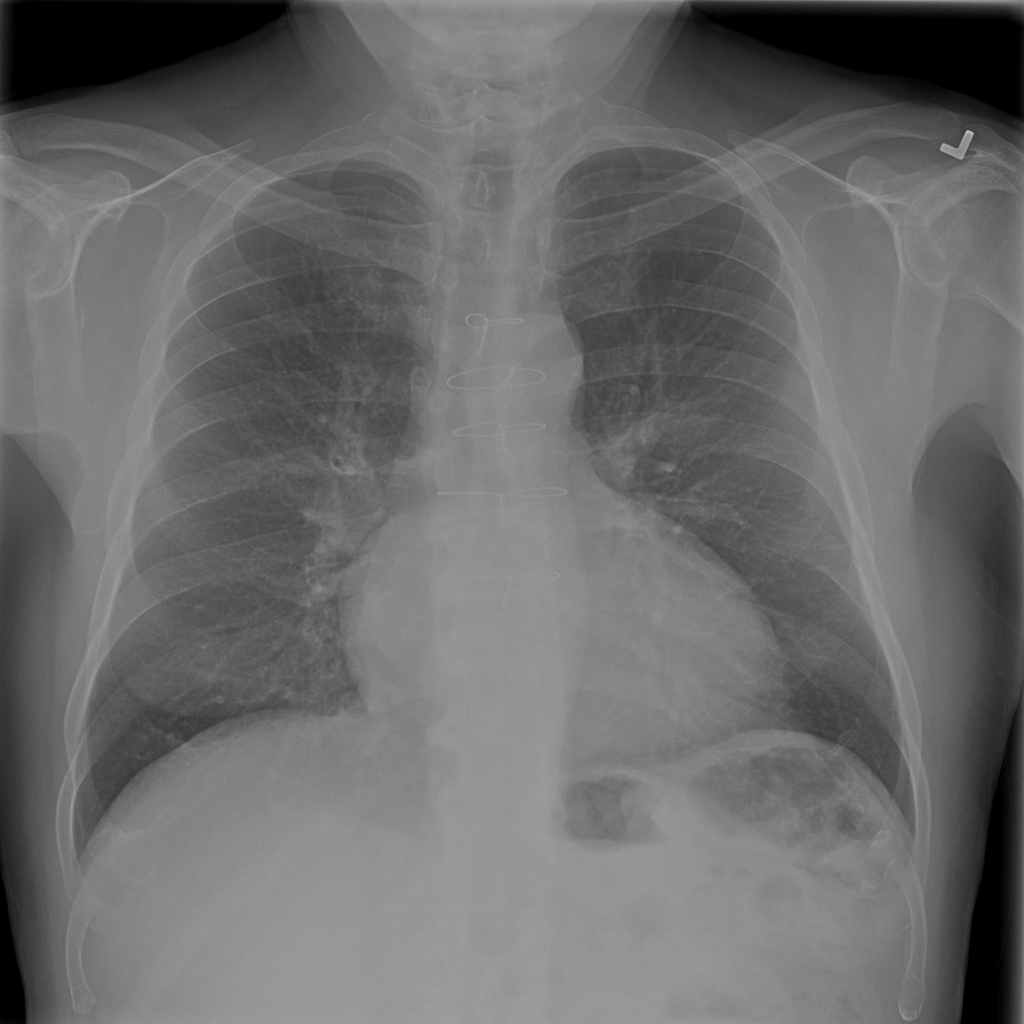

PAT-AE5C · IMG-000Cardiomegaly

PAT-AE5C · IMG-000

PA